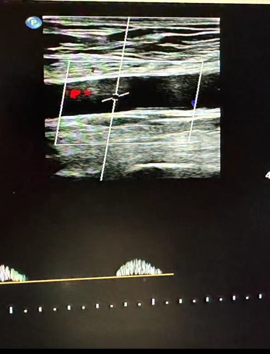

然而,蹊跷之处随之浮现。医生仔细扫查了患者从股动脉直至腹主动脉的整条下肢供血通路,血管结构清晰,未见明显狭窄或斑块。

经验丰富的医生判断问题可能潜藏在更近心端的胸主动脉,但该区域受胸骨遮挡,常规超声探查受限。